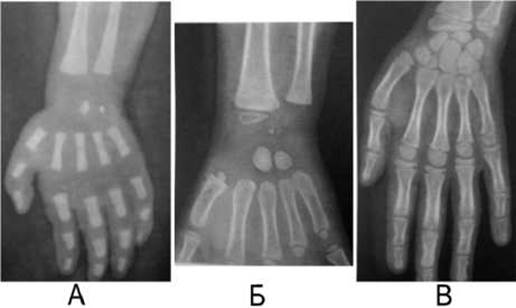

За наявністю і синостозуванням додаткових ядер окостеніння у судовій медицині можна визначити приблизний вік людини (мал. 31). Наприклад, ядра окостеніння в ділянці зап’ястка з’являються у такі строки: головчастої кістки - на третьому-четвертому місяці життя, гачкуватої кістки - на п’ятому-шостому місяці, дистального епіфізу променевої кістки - наприкінці першого року життя, тригранної - наприкінці другого року, півмісяцевої - наприкінці третього року, човноподібної - на четвертому-п’ятому році, кістки-трапеції - на п’ятому році, трапецієподібної кістки - на шостому році, дистального епіфізу ліктьової кістки - до семи років, горохоподібної - на 11-13 році життя.

У дитячому віці вторинні ядра скостеніння відокремлені від основної кістки ростковою зоною хряща, представленого на рентгенограмі смужкою просвітлення. Ширина цієї смужки з ростом дитини поступово звужується, а в період синостозування зникає. Після синостозування ядра скостеніння епіфіза з діафізом інколи залишається метафізарний шов, і у дорослих у колишній зоні росту спостерігається лінійна вузька тінь. Суглобова рентгенівська щілина у дітей розширена, з віком вона поступово звужується, і після 17-20 років ширина їх становить близько 3-4 мм.

Таким чином, рентгенограми кісток та суглобів дітей характеризуються наявністю: 1) точок окостеніння епіфізів; 2) смуги просвітлення на місці метафізарного хряща; 3) значної висоти рентгенівської суглобової щілини.

Мал. 31. Рентгенограми кисті дитини у віці 1 року (А), 3 років (Б), 7 років (В).